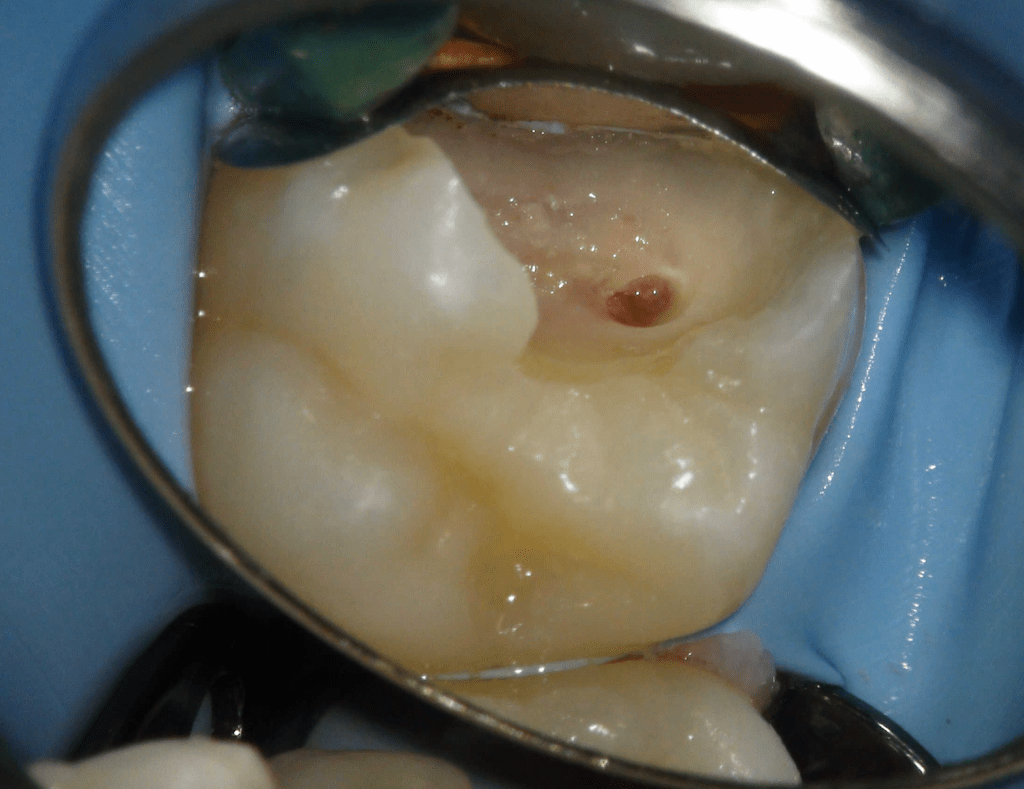

Pulpotomía biodentine + reco preendio